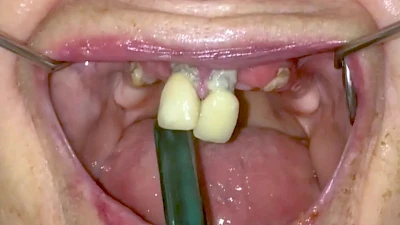

Eine geringe spürbare Beweglichkeit der Zähne ist durchaus normal, da Zähne über Fasern im Kieferknochen aufgehängt sind. Lassen sich Zähne, Kronen oder Brücken jedoch deutlich sichtbar bewegen, besteht die Gefahr, dass sie sich lösen und verschluckt oder aspiriert werden. Deshalb sollte in diesen Fällen der Zahnarzt verständigt werden.